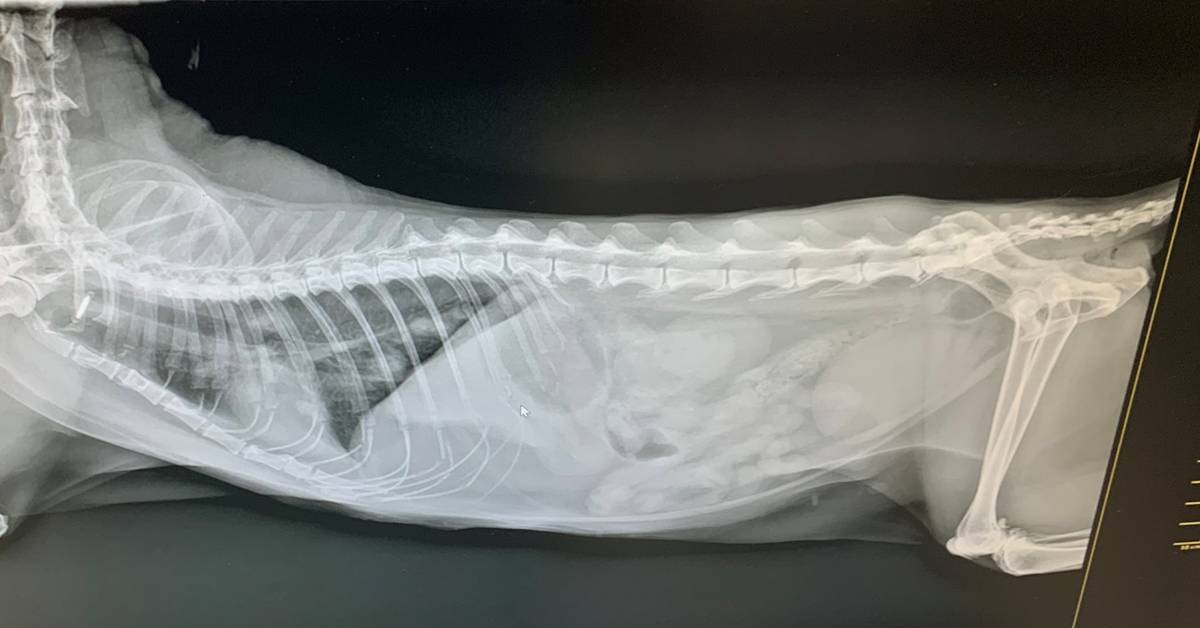

放射影像學

影像學中,脊椎的部分並無明顯異常。肺臟部分有看到結構性間質相 (高度懷疑乳腺瘤轉移),以及輕微的支氣管相。膀胱的部分則明顯有變大。